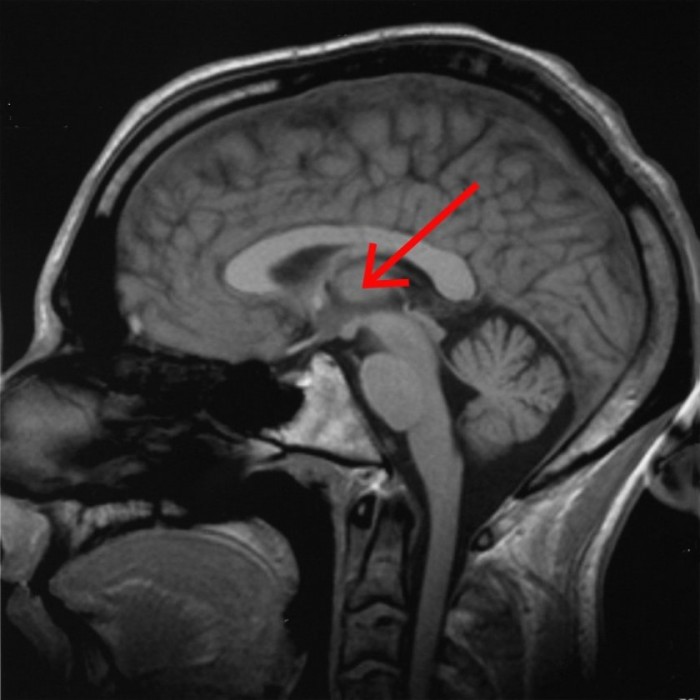

据外媒New Atlas报道,关于人体和大脑的运作,我们还了解得不是很多,而意识本身仍然是科学的重大奥秘之一。神经科学的中心问题之一是弄清楚在大脑意识中何处出现,这是体验内在和外在感觉的能力。研究人员报告说,大脑的特定区域,即中央外侧丘脑,似乎发挥着关键作用。

长期以来,科学家一直在研究位于大脑深处脑干附近的丘脑,以了解丘脑在睡眠、苏醒、意识和机敏性中起什么作用。但是这项针对特定区域应用电刺激的研究使搜索范围比以往任何时候都缩小了。研究中使用的电极更适合他们设计要工作的大脑结构的形状,电刺激旨在模仿正常的醒来的大脑的活动。

研究人员以猕猴为动物模型。通过研究清醒、睡眠和麻醉的动物,他们能够将意识中涉及的大脑区域缩小到比其他研究更为具体的区域。他们还能够排除先前意识相关的神经相关研究中提出的某些领域。他们最终集中在前脑深处的中央外侧丘脑。